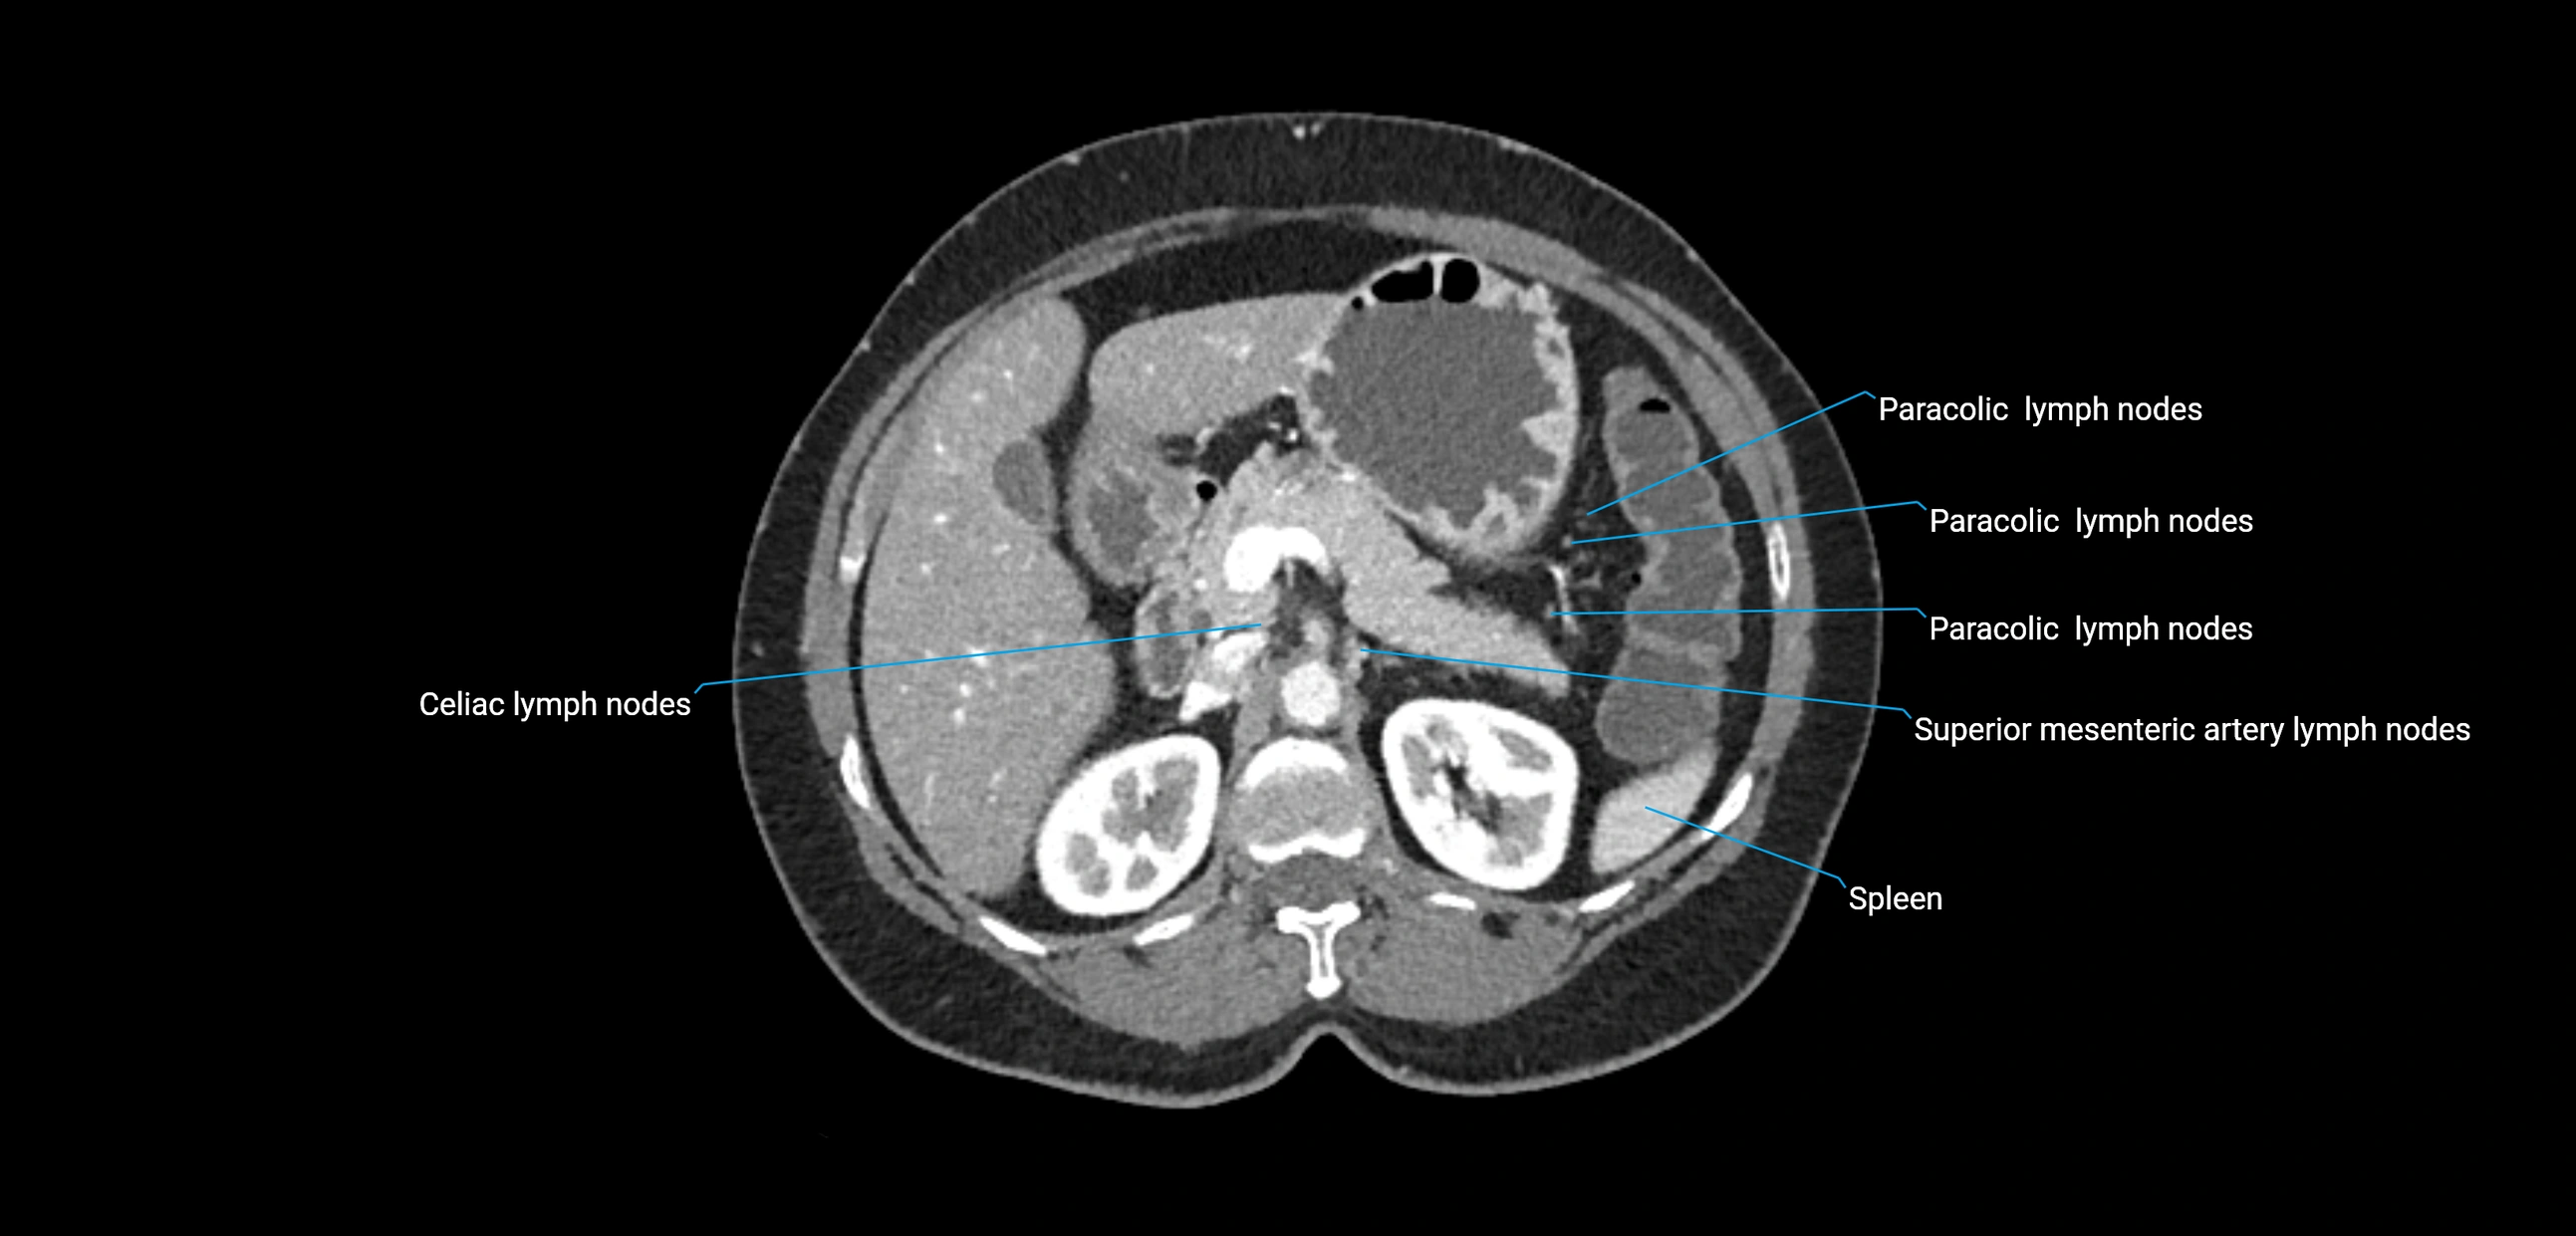

CT Appearance

CT Pre-Contrast:

• Nodes appear as soft-tissue density nodules adjacent to the aorta and IVC

• Calcification may be seen in chronic infections (e.g., tuberculosis)

CT Post-Contrast:

• Normal nodes enhance homogeneously

• Malignant nodes may show heterogeneous enhancement, central necrosis, or conglomerate formation

• Size >1 cm short axis is suspicious, though morphology and distribution are equally important

CT Venography (CTV):

• Demonstrates nodal encasement or compression of adjacent vessels (aorta, IVC, renal veins)

• Useful in staging testicular and ovarian malignancies

• Provides 3D reconstructions for retroperitoneal lymph node dissection planning